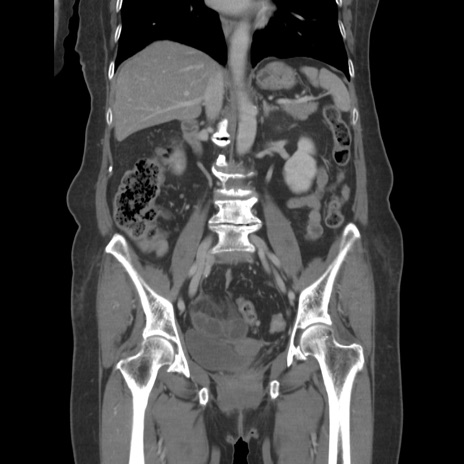

症例19(冠状断像)

【症例】80歳代女性

【主訴】下腹部痛

【現病歴】約8時間前より下腹部痛の出現あり、救急外来受診。

【既往歴】両側付属器切除

【身体所見】意識清明、下腹部正中に手術痕あり、その部位に一致して圧痛と反跳痛あり。腸蠕動音は亢進。

【データ】WBC 9300、CRP 0.15